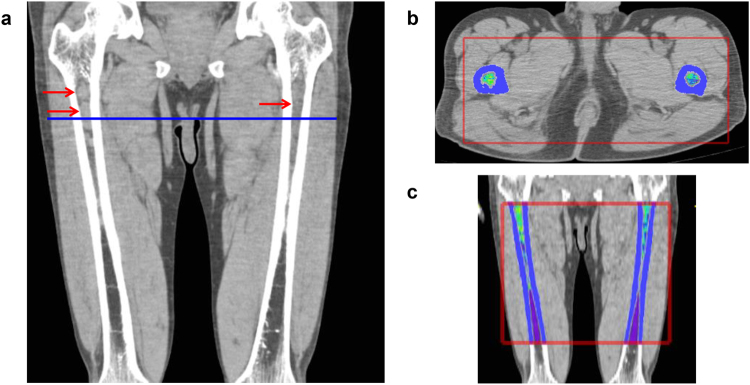

To determine a three-dimensional volume-of-interest and calculate the sum of CT values in one appendicular skeleton, the software set horizontal and vertical ranges on axial CT images. The horizontal range (x and y-axis) (e.g., shown as the red rectangle in Fig. 1b) included a bone marrow area surrounded by circular cortical bone. The software automatically recognized circular regions with CT values higher than 120 HU as cortical tubular bones. The vertical range (z-axis) (e.g., shown as the red rectangle in Fig. 1c) was anatomically defined by the operators to include the diaphysis and proximal and distal metaphysis and to exclude the proximal and distal epiphysis, as the trabecular architecture of the epiphysis expresses very high (over 120 HU) CT values. Once horizontal and vertical ranges in each appendicular skeleton had been selected, the software automatically extrapolated the ranges rest of the slices, and calculated cCTv for all the voxels within the selected bone.

Figure 1.

Representative images of a patient with advanced IgAκ myeloma. (a) Coronal CT image of the femora. Myeloma infiltration was detected in the upper metaphysis and diaphysis in both the left and right femora (arrows). (b) Axial image at the level of the blue line shown in (a). The software provides pseudo-colour according to the Hounsfield unit (HU) (high: yellow-red, low: blue-purple). (c) Coronal image reconstructed from the axial slices. Red rectangle: horizontal and vertical ranges for the determination of cumulative CT value (cCTv). The cCTv of this case was 4.46 HU.